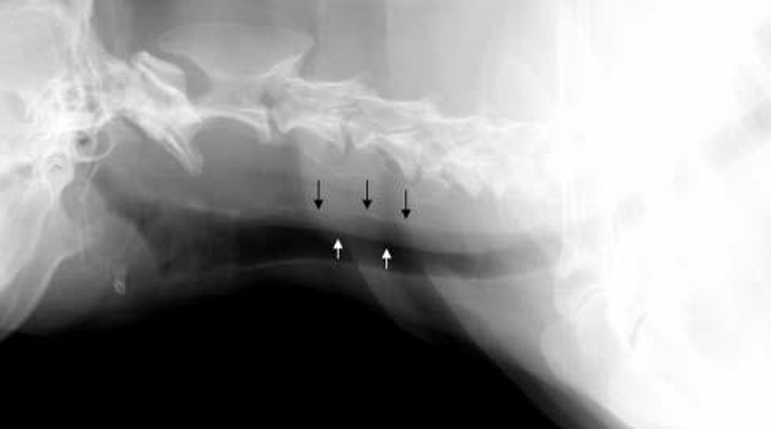

| ๊ฒฝ๋ถ ๋ฐฉ์ฌ์ | |

![]() | - ๊ฒฝ๋ถ ์ชฝ lateral ์ดฌ์์์ trachea์ dorsal ์ชฝ์ผ๋ก ๊ฒน์น ์์์ด ๋ณด์. - Trachea์ dorsal band๊ฐ ์ถ ์ณ์ ธ์ ์ด๋ ๊ฒ ๋ณด์ผ ์๋ ์์ง๋ง (์ด ๊ฒฝ์ฐ๋ tracheoscopy๋ก ๊ฐ๋ณ + dorsal membrane์ด ์ถ ๋์ด์ง๋ฉด trachea๊ฐ ๋ฌด๋์ง๋ ๊ฒฝํฅ), - ์ฐ๊ณจ ์์์ด ์ด์ง ๋ณด์ด๋ฉด์ diameter๊ฐ ์ผ์ ํ ๊ฒ์ ๋ณด๋ฉด ์๋์ ๊ฒน์น ๊ฒ์ผ๋ก ๋ณด๋ ๊ฒ์ด ํ๋น. |